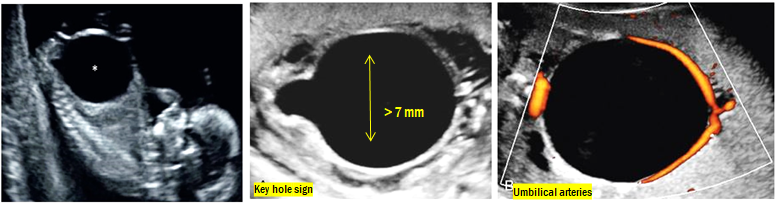

- : Bladder임을 확인하는 첫번째 방법은 umbilical arteries를 Doppler flow로 확인하는 것입니다.

- : Bladder의 longitudinal diameter가 7 mm 이상이면 megacystis라 명명합니다.

Posterior urethral valves: 남아, Key hole sign이 중요한 clue입니다. 정상 urethra에는 없는 valve가 prostate가 끝나는 지점에 존재하여 urine이 빠져나가지 못해 prostate urethra부터 bladder까지 dilation이 되는 질환입니다. 주수가 지날수록 악화되어 hydronephrosis를 동반하기도 합니다.